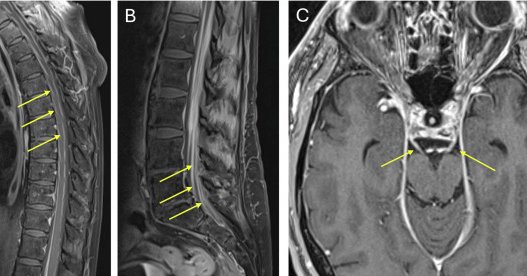

1 month

Our recent article will be featured as Cover Art for the December issue of Journal of Neuroimmunology! Grateful to my co-authors, and to the patient for allowing us to share his story. Link to article: https://t.co/ciwPcqDZgj #AutoimmuneEncephalitis #NorthwellHealth #LenoxHill